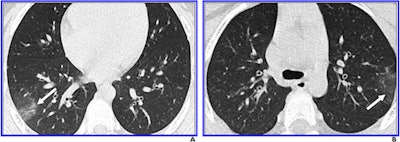

8-year-old boy with COVID-19. A and B, Unenhanced chest CT scans show minimal ground-glass opacification (right lower and left upper lobes) (arrows) and no consolidation. Only two lobes were affected, and CT findings were assigned a CT severity score of 2. Images courtesy of the American Journal of Roentgenology.The study demonstrates that negative findings on CT don't necessarily rule out COVID-19.

Steinberger and colleagues found that 77% of chest CT findings in the patient cohort were negative (23 of 30 children). Seven of the 30 patients had positive chest CT findings (as well as at least one clinical symptom on presentation); these findings were characterized by ground-glass opacities with peripheral distribution, the "crazy paving" pattern, and halo and reverse halo signs.

There were no pleural effusions or lymphadenopathy on chest CT in the patient cohort. Steinberger and colleagues noted that the severity of CT findings in the children increased with age. Of the 30 children, 11 (37%) underwent follow-up chest CT, and of those 11 exams, 10 (91%) showed no change.